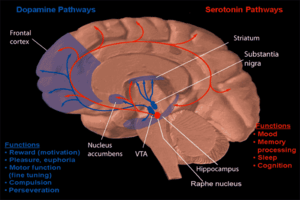

Input

Major inputs to the nucleus accumbens include the prefrontal cortex, basolateral amygdala, and dopaminergic neurons located in the ventral tegmental area (VTA), which connect via the mesolimbic pathway. Thus the nucleus accumbens is often described as one part of a cortico–basal ganglia–thalamic loop.[11]

Dopaminergic input from the VTA modulate the activity of neurons within the nucleus accumbens. These neurons are activated directly or indirectly by euphoriant drugs (e.g., amphetamine, opiates, etc.) and by participating in rewarding experiences (e.g., sex, music, exercise, etc.).[12][13]

Output

The output neurons of the nucleus accumbens send axonal projections to the basal ganglia and the ventral analog of the globus pallidus, known as the ventral pallidum (VP). The VP, in turn, projects to the medial dorsal nucleus of the dorsal thalamus, which projects to the prefrontal cortex as well as the striatum. Other efferents from the nucleus accumbens include connections with the tail of the ventral tegmental area,[16] substantia nigra, and the reticular formation of the pons.[1]

Dopamine and serotonin

Dopamine and serotonin- MRI coronal slice showing nucleus accumbens outlined in red